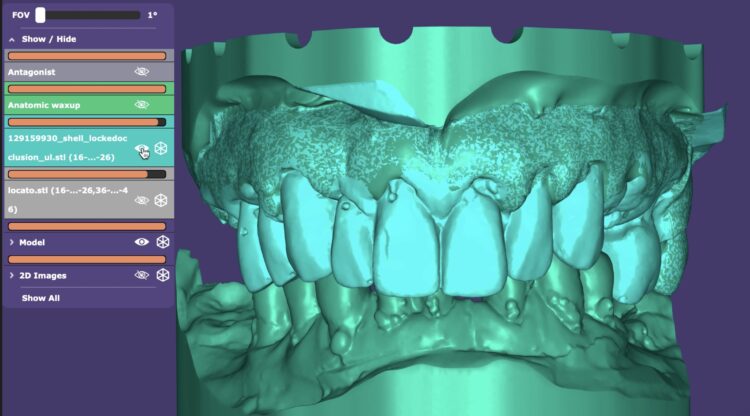

When ready, the surgical planning involved a fully digital, prosthetically-driven workflow, with full dentist and dental technician collaboration. Intraoral scans (IOS) were merged with the DICOM data from the CBCT to optimise data capture and facilitate an accurate digital plan for implant placement and prosthesis design. The digital files and photographs were imported into a Digital Design Software (EXOCAD) and a personalised, facially-driven tooth library was used to perform an initial virtual wax-up.

The use of a surgical guide for the accurate and precise placement of the dental implants was chosen in this case. The positions and angulations of the implants were planned according to the ideal virtual wax-up that was produced. We decided to create a tooth-supported acrylic guide for fully guided surgery, supplemented by bone-fixed anchor pins for enhanced stability. The most appropriate teeth for this were identified during this planning phase.

After four months, an IOS impression was executed and a digital dataset created superimposing the soft tissue, implant scan bodies, antagonist and temporary prosthesis scanning files. To avoid any inaccuracy in scalloped interface reproduction due to quick collapse of the gingival tissue, the provisional prosthesis was scanned both intraorally and extraorally, capturing its overall contour and, in particular, the transmucosal surface at the pontic sites and emerging profiles.

A titanium substructure was digitally designed (Bridge Base by Atlantis) taking into consideration the functional and aesthetic virtual wax-up and emergence profile as the FP1 provisional prosthesis shaped it. This metal substructure was anatomically shaped at the gingival and occlusal sides in order to tightly adhere at the soft tissue interface leaving at least 2mm of clearance for the zirconia superstructure.